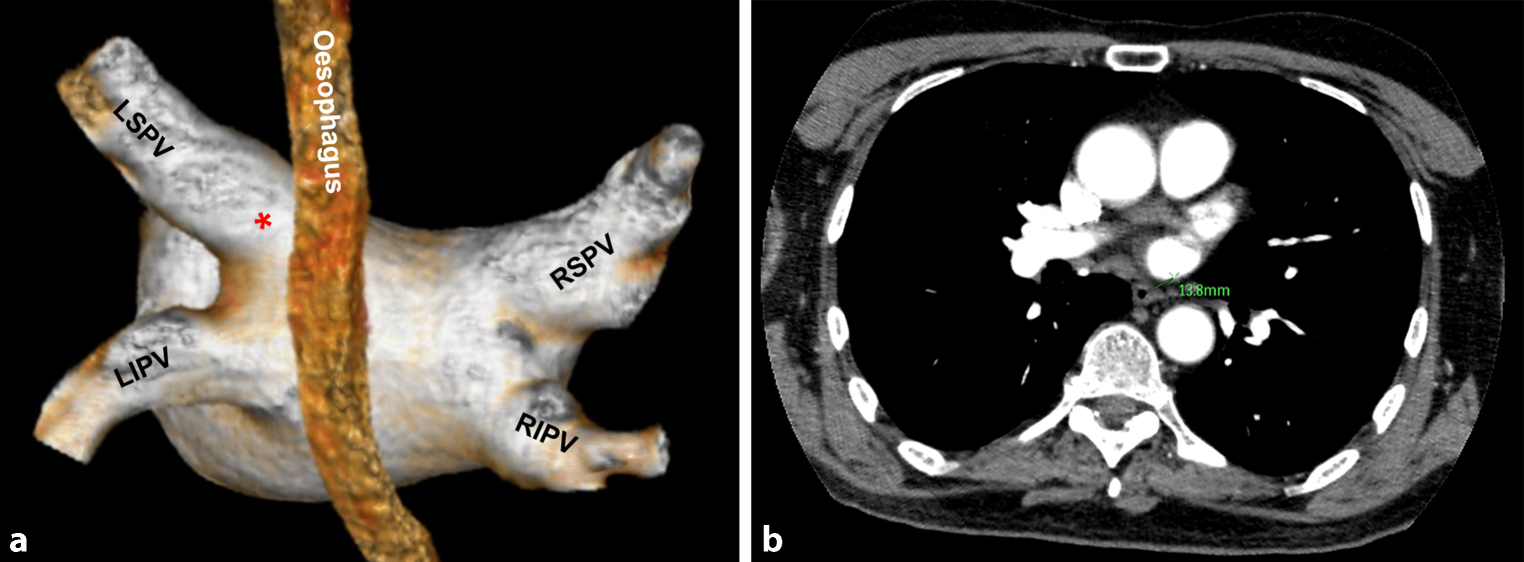

CT measurements

For this study the CT images acquired pre-PVI were used to measure the shortest distance between the oesophagus and the os of every PV (OP distance). To measure this OP distance, the origin of the os was identified as the indentation in the posterior wall, caused by the angulation of the PV compared to the atrial wall (Fig. 2a). Since the oesophagus runs perpendicular to the axial plane, the distance from the identified angulation to the oesophagus in the axial plane represents the shortest OP distance. This distance was measured (Fig. 2b).

a Shortest oesophagus to pulmonary vein distance measurement when we first looked at the CT images. The origin of the os, identified as the indentation in the posterior wall, caused by the angulation of the pulmonary vein compared to the atrial wall. The angulation between the pulmonary vein and the atrium can be well distinguished in this 3D view. The distance from the identified angulation (*) to the oesophagus in the axial plane represents the shortest oesophagus to pulmonary vein distance. LSPV left superior pulmonary vein, RSPV right superior pulmonary vein, LIPV left inferior pulmonary vein, RIPV right inferior pulmonary vein. b This distance was measured